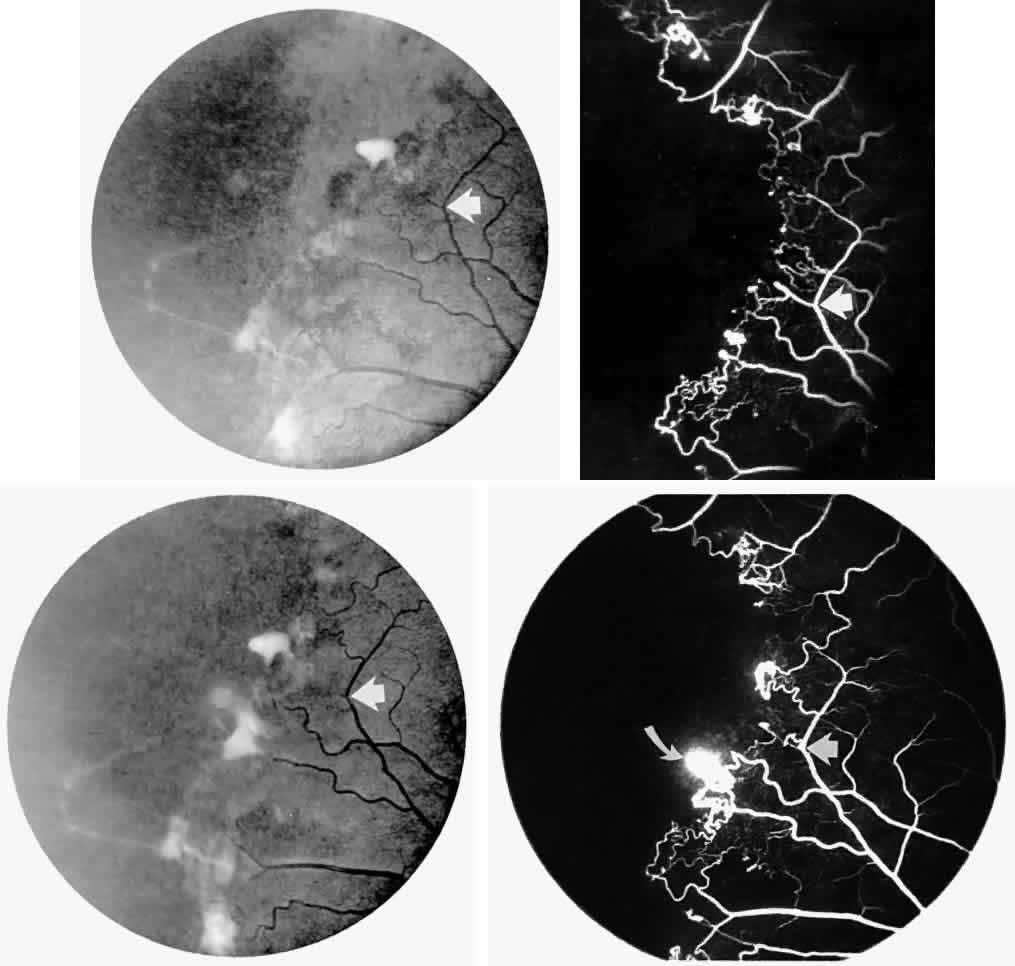

Occlusions of the fine vasculature of the macular and perimacular area have been reported in 10% to 40% of patients with sickle cell disease.18,83,91–99 In the acute phase, the occluded vessel will have a dark red appearance and may appear as a dark line on fluorescein angiography (Fig. 9). Nerve fiber layer infarcts (cotton-wool spots) are seen (see Fig. 8D and E;Fig. 10).100

Fig. 9. A 27-year-old man with homozygous sickle cell anemia. A. Fluorescein angiogram of the right eye shows multiple arteriolar occlusions temporal to the fovea (arrows). B. Same area 6 months later shows more extensive occlusions. The black arrowheads (A and B) identify corresponding arteriolar bifurcation.

Fig. 10. A 33-year-old woman with SC disease and stage III sickle cell retinopathy. A. Photograph of the right eye shows a cotton-wool spot with a dark segment identifying the occluded vessel (arrow). B. Fluorescein angiogram demonstrates nonfilling of the occluded vessel (arrow). C. Eighteen months later, the occluded vessel is still visible (arrow). D. Fluorescein angiogram demonstrates that there is still nonfilling of the vessel (arrow).